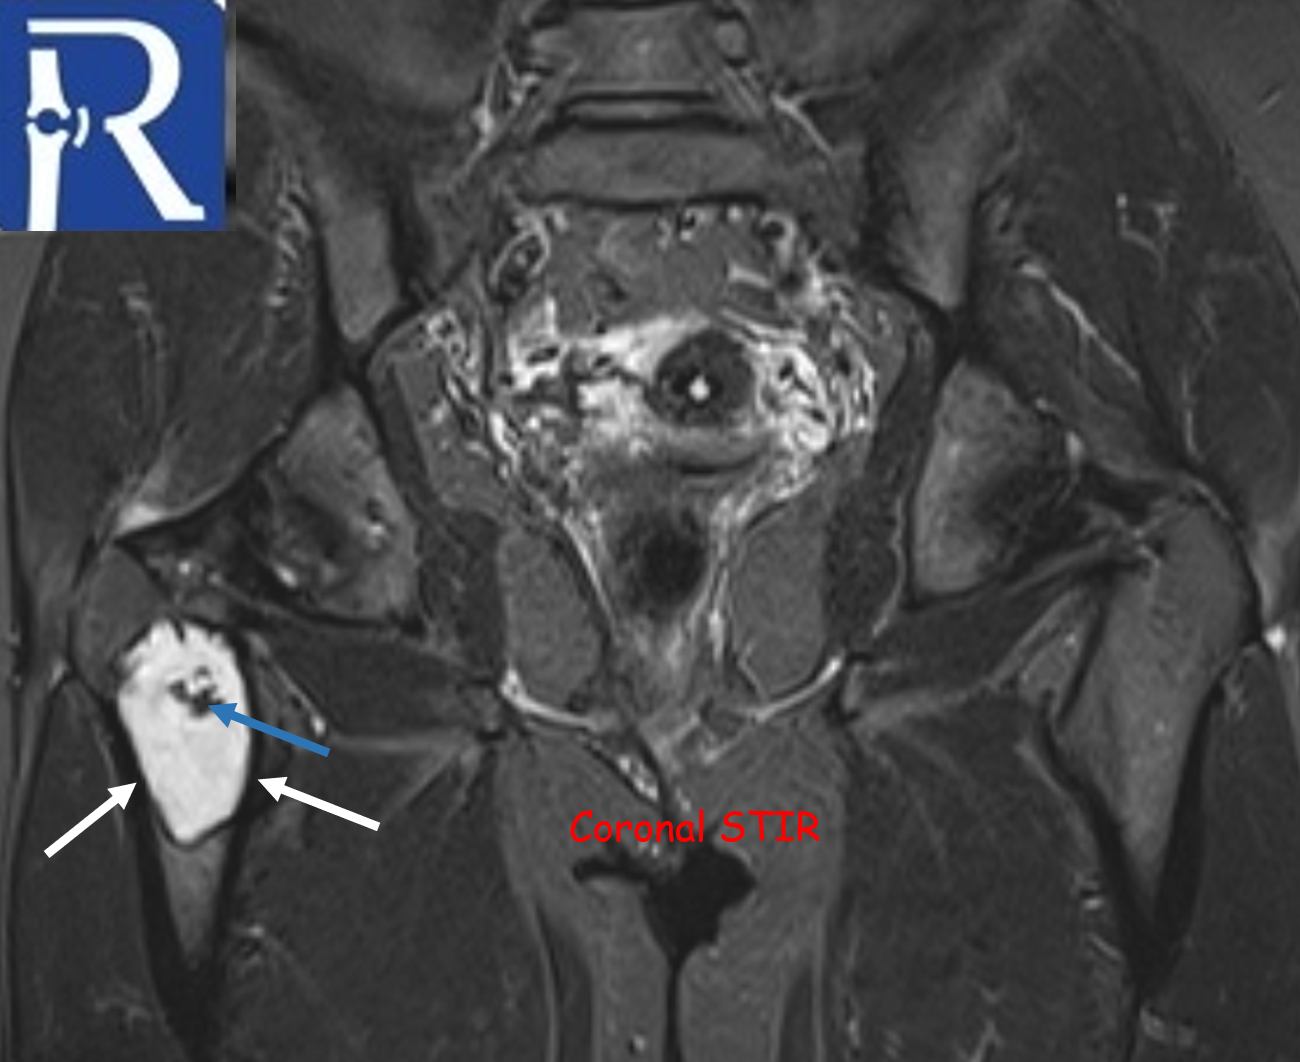

A geographic lytic lesion of Type I A pattern (white arrows) is observed on the right femur intertrochanteric-subtrochanteric area on the pelvic radiograph. The lesion is well-circumscribed and has a narrow transition zone. The internal content contains calcification (indicated by the blue arrow). Periosteal reaction is not visualised. The lesion demonstrates sclerotic areas corresponding to internal calcified foci. The lesion is compatible with liposclerosing myxofibrous tumors. In CT, the lesion matrix structures are more clearly visible, and the cortex appears intact. Calcification areas in the internal structure are more clearly observed. In MRI, the lesion appears as a low signal on the T1-weighted (T1W) sequence and as a high signal on the short tau inversion recovery (STIR) sequence, representing the myxoid content. Additionally, the calcification areas within the lesion exhibit low signals in both sequences.